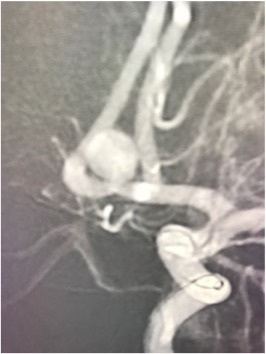

Gehirnaneurysma (Clip, Coil, Flow Diverter)

Als klinisch-wissenschaftlicher Neurochirurg habe ich großes Interesse daran, meine klinischen Aufgaben durch Wissenschaft und Forschung in den von uns behandelten neurochirurgischen Erkrankungen zu ergänzen. Seit meinem Studium und postgraduellen Ausbildung war ich an Grundlagenforschung, klinischer und translationaler Forschung beteiligt und habe bisher mehr als 450 wissenschaftliche Veröffentlichungen zur medizinischen Fachliteratur beigetragen sowie erfolgreich kompetitive Drittmittel eingeworben. Wir haben die Behandlung traumatischer zerebrovaskulärer Erkrankungen, genetische Polymorphismen im Zusammenhang mit zerebralen Aneurysmen und aneurysmatischen Subarachnoidalblutungen sowie die Behandlung von Thrombozytenaggregationshemmern im Zusammenhang mit der Flow-Diverter-Behandlung von zerebralen Aneurysmen untersucht, um nur einige Projekte zu nennen.